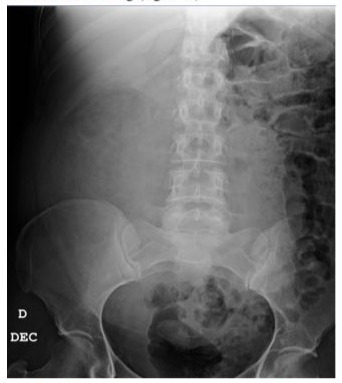

Patient A arrived at the Emergency department after experiencing two episodes of presyncope, which were accompanied by severe abdominal pain. A physical examination revealed a palpable abdominal tumor. The abdominal x-ray showed a large mass that had displaced the bowel (figure 1). Additionally, a CT scan showed findings compatible with Wunderlich syndrome, but there was no evidence of active bleeding (figure 2).

Figure 1: The abdominal x-ray reveals the displacement of the bowel loops into the left hemiabdomen.